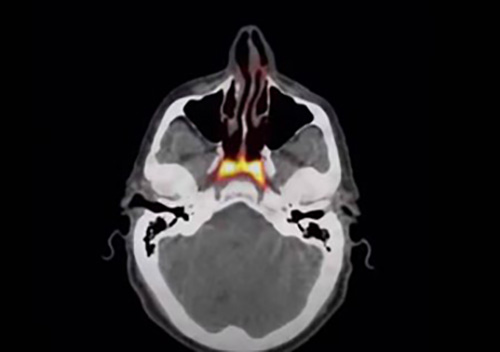

پژوهشگران هلندی زمانی که مشغول بررسی وضعیت بیماران مبتلا به سرطان پروستات بودند، مقداری گلوکوز رادیواکتیو را به بدن این افراد تزریق کردند. چنین روشی در کنار استفاده از اسکن PSMA PET/CT میتواند محل دقیق تومورها در بدن انسان را مشخص کند؛ اما در کمال تعجب، ماده مورد نظر در قسمت دیگری از بدن و جایی که کسی انتظار آن را نداشت، ظاهر شد. دانشمندان مشاهده کردند که گلوکز رادیواکتیو به کار رفته پشت قسمت بالایی حلق را نورانی کرده بود.

ووگل و تیمش به کمک دستگاه PSMA PET/CT تمامی صد بیمار مبتلا به سرطان پروستات داوطلب شده برای تحقیقات را مورد بررسی قرار دادند و به علاوه، برای تایید وجود این جفت غده در بدن انسان، جسد یک زن و مرد هم کالبدشکافی شد. همانطور که انتظار میرفت، غدههای لولهای شکل مورد نظر در همان قسمتی که اعلام شده، قرار داشتند.

محققان میگویند که مجراهایی برای ترشح بزاق در این غدهها وجود داشت و در کمال تعجب، توصیفات پیشین دانشمندان و آناتومی شناسان از ساختار این قسمت از سر انسان، با آنچه اسکن جدید نشان میدهد، تطابق ندارد. گفته شده که به احتمال قوی، نقش این اندام ناشناخته بدن به وجود آوردن مایعاتی بوده که به هنگام قورت دادن و مرطوبسازی قسمت بالایی سقف دهان، به کار میآیند.